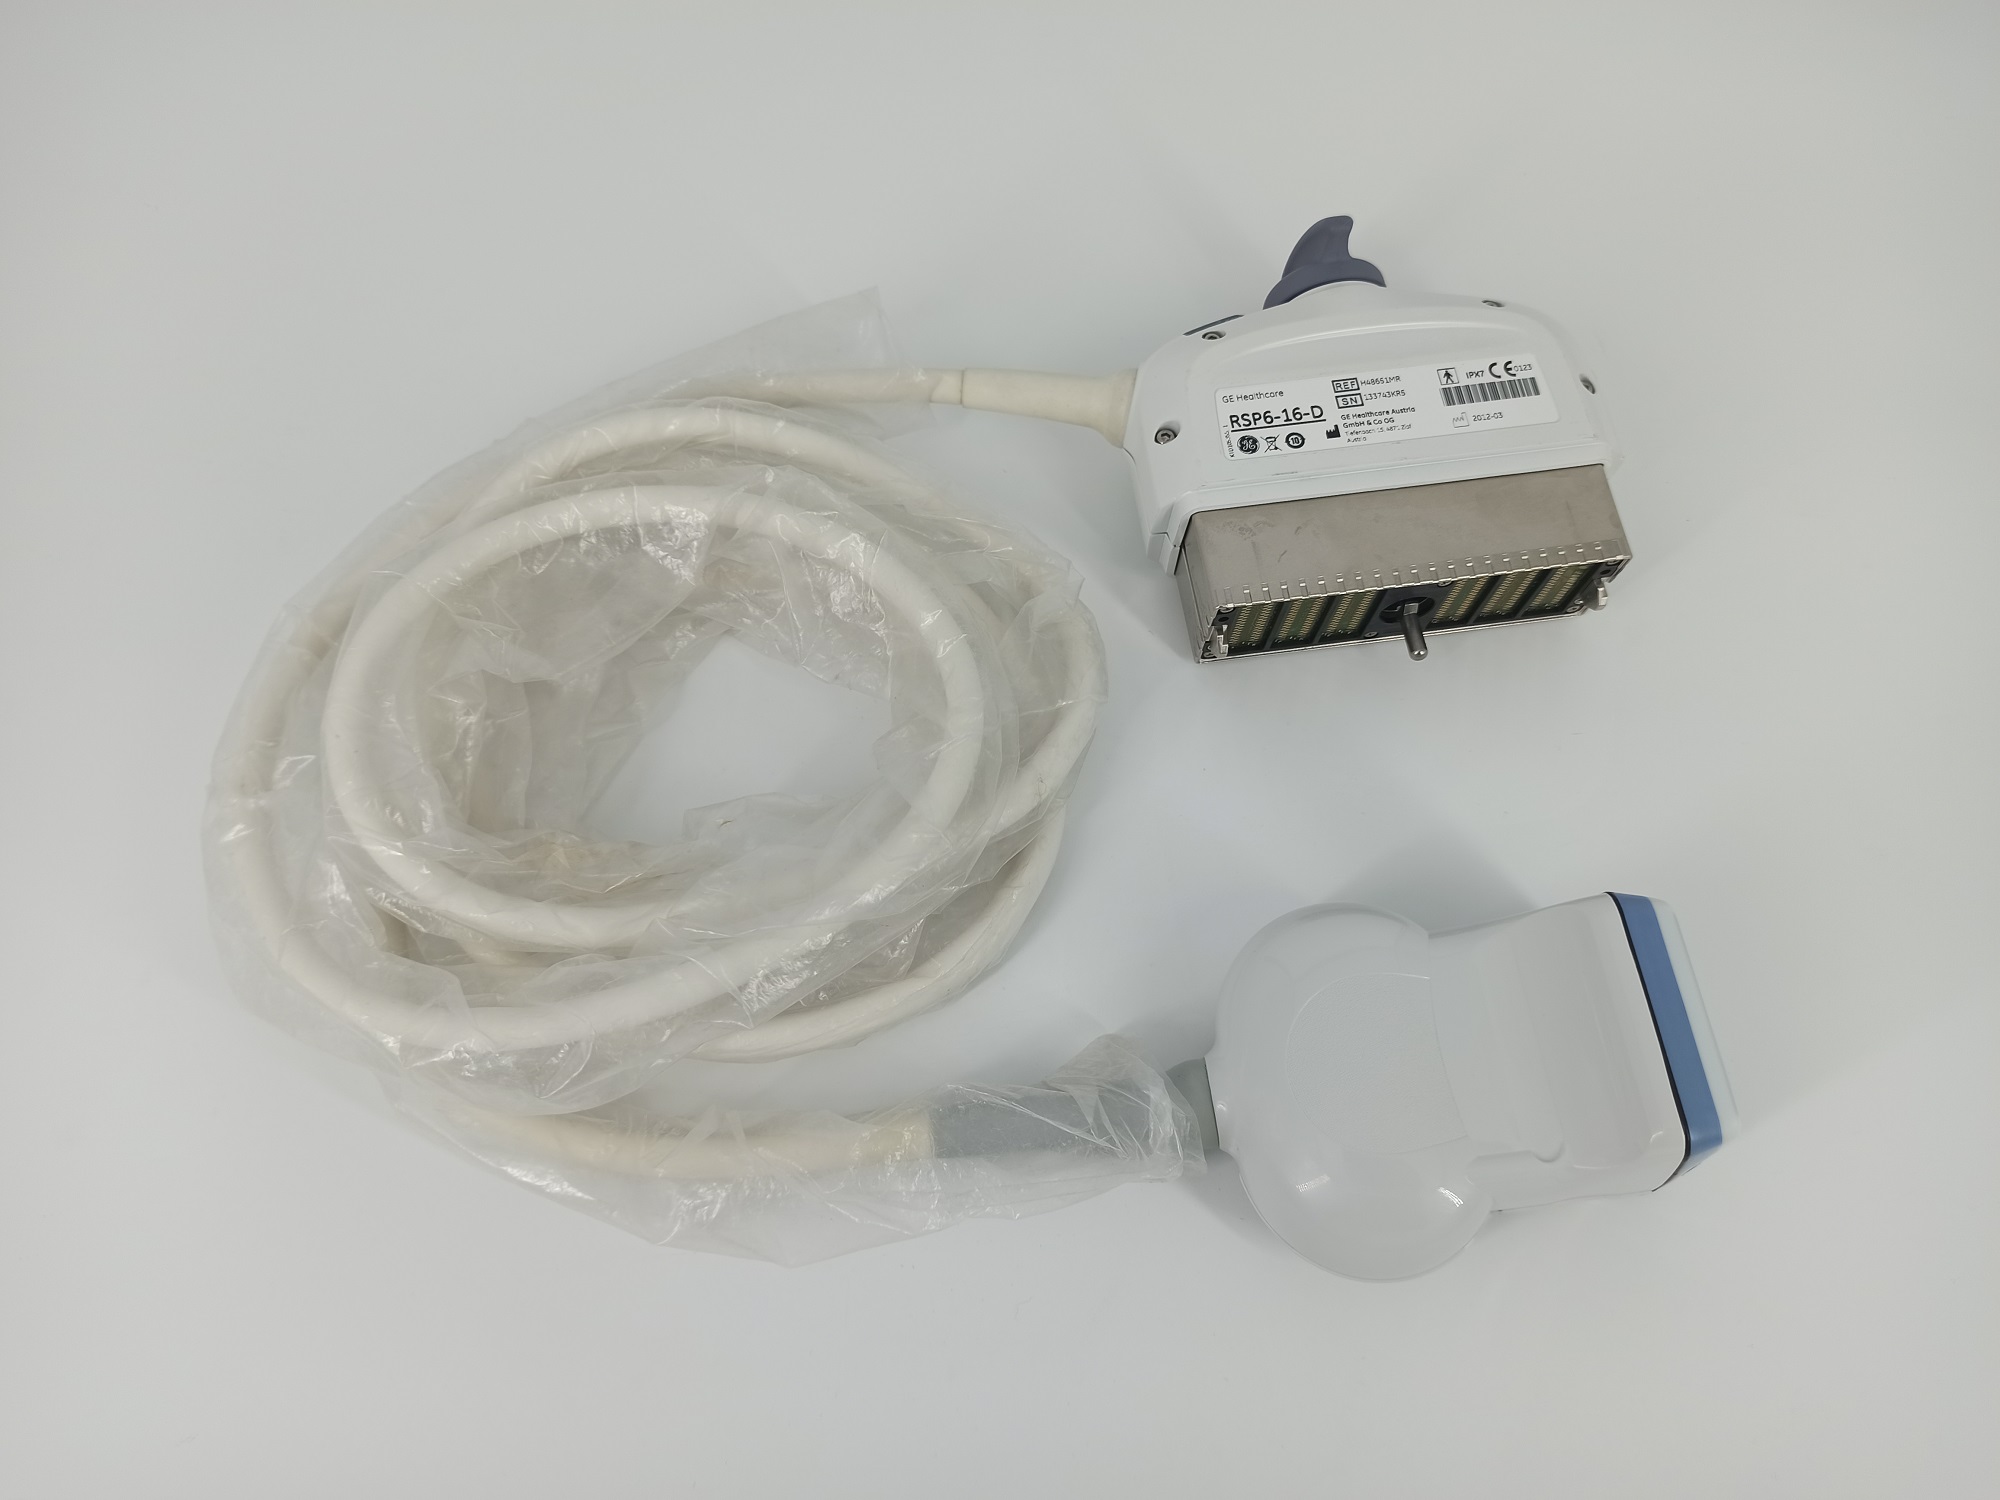

GE RSP6-16-D 3D/4D Linear Refurbished

GE RSP6-16-D 3D/4D Linear

SKU: RSP6-16-D-ref

GE RSP6-16-D 3D/4D Linear

GE RSP6-16-D 3D/4D Linear for Breast, Small parts, Vascular and Musculoskeletal